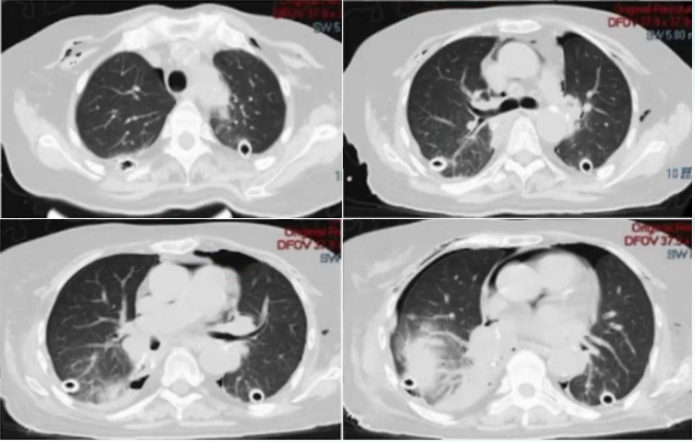

• 胸部CT(移植前):双肺多发间质改变,胸膜下为著,局部可见网格影、蜂窝影及牵拉支扩,以及沿支气管血管束分布的磨玻璃影(图1)

1  患者移植前胸部CT